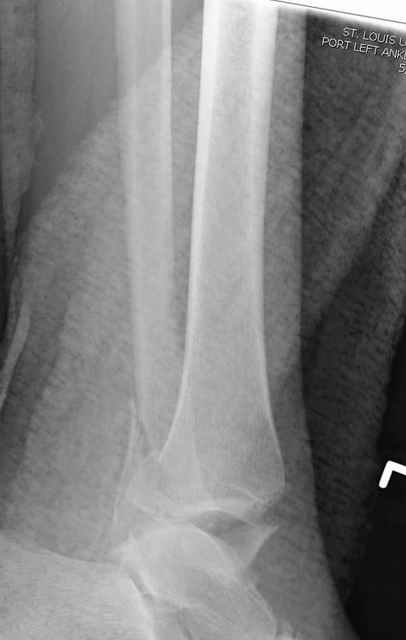

Pilon fracture:

-Появляется ориентир и остов, на чем можно строить восстановление, почему сперва малоберцовую, впервые обьяснили и описали (Pylon type and Ankle fractures) в середине 50х Rienau и Gay.

Восстановливая длину и ротацию малоберцовой кости, затем относительно легче произвести реставрацию остальных элементов перелома дистального эпиметафиза болшеберцовой кости.

где исследования на трупах показали, что малоберцовая кость участвует в стабильности голеностопного сустава, поддерживая наклон тарана (talar tilt) за счет связок. После ознакомления работой Ramsey в ортопедию ввели термин "при переломах голеностопного сустава смещенная

таранная кость следует за малоберцовой костью" т.е. связка не рвется, а тянет таран за собой, поэтому восстановление малоберцовой кости в

первую очередь, затем остальных элементов - стал классическим при лечении данной патолгии. Латеральная колонна (столб), дистальный

конец малоберцевой кости, к нему прикрепляется латеральный суставной фрагмент дистального эпиметафиза большеберцовой кости (как на снимке)

и таранная кость, которые при репозиции малоберцовой кости репонируются автоматически.

Из работ Ramsey and Hamilton, Yablon et., укорочения на 1мм

малоберцовой кости, уменьшает на 42% контактную поверхность между

малоберцевой и таранной кости, которое в свою очередь приводит к

увеличению давления на остальные части суставной поверхности, что

является предпосылкой раннего артроза.